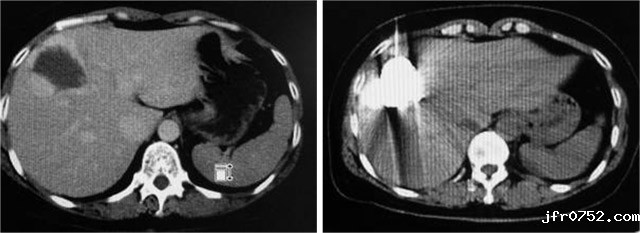

以下是成功病例的CT影像对比:

男,68岁,肝左叶巨大血管瘤,肝动脉栓塞后,肿瘤消失

女,48岁,肝右叶海绵状血管瘤,CT引导经皮穿刺平阳霉素碘油乳剂注射